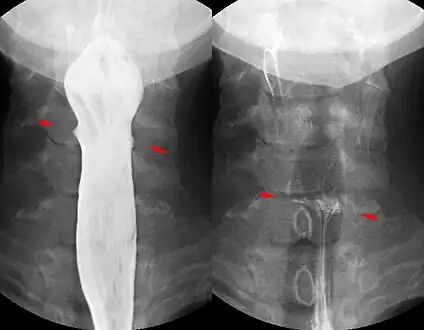

Contrast compounds containing barium or iodine, which are radiopaque, can be ingested in the gastrointestinal tract (barium) or injected in the artery or veins to highlight these vessels. The contrast compounds have high atomic numbered elements in them that (like bone) essentially block the X-rays and hence the once hollow organ or vessel can be more readily seen. In the pursuit of nontoxic contrast materials, many types of high atomic number elements were evaluated. Some elements chosen proved to be harmful – for example, thorium was once used as a contrast medium (Thorotrast) – which turned out to be toxic, causing a very high incidence of cancer decades after use. Modern contrast material has improved and, while there is no way to determine who may have a sensitivity to the contrast, the incidence of serious allergic reactions is low.[1]

X-rays are also used in "real-time" procedures such as angiography or contrast studies of the hollow organs (e.g. barium enema of the small or large intestine) using fluoroscopy. Angioplasty, medical interventions of the arterial system, rely heavily on X-ray-sensitive contrast to identify potentially treatable lesions.